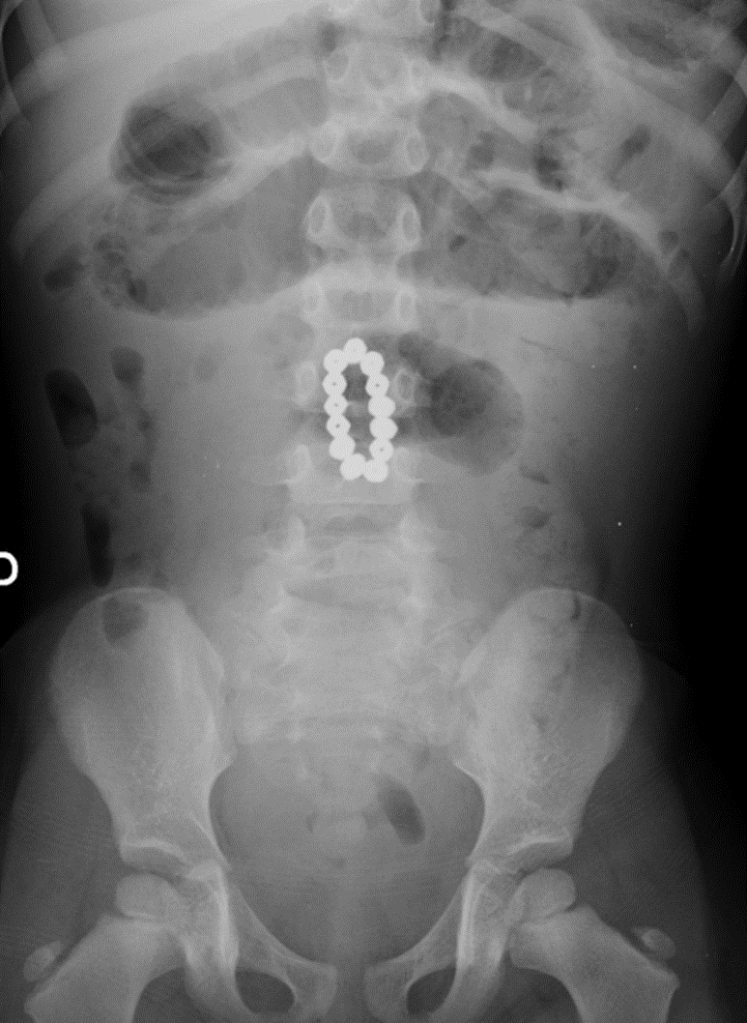

INGESTA DE CUERPOS EXTRAÑOS (SOBRE TODO EN PEDIATRÍA O PACIENTES PSIQUIÁTRICOS).

La ingesta de cuerpos extraños no alimentarios, inadvertida o intencionalmente, es una situación habitual en las consultas de pediatría. Exceptuando los objetos grandes o afilados, la gran mayoría progresarán espontáneamente a través del tubo digestivo sin consecuencias.